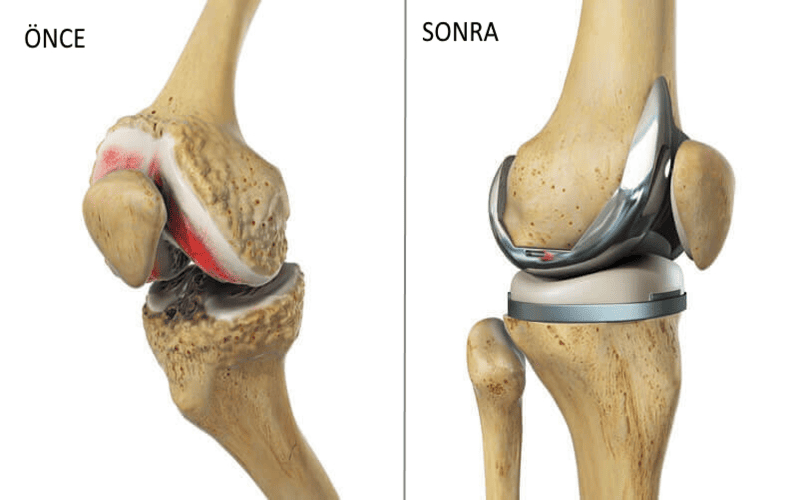

Artroplasti, ileri derecede hasar görmüş eklemlerin cerrahi olarak çıkarılması ve yerine yapay protez eklemler yerleştirilmesidir. Bu işlem, eklemin fonksiyonunu geri kazandırır ve ağrıyı ortadan kaldırır. Op. Dr. Sercan Karadeniz, Trabzon’da artroplasti alanında modern cerrahi teknikler ve yüksek kaliteli protezler kullanarak hastalarına uzun ömürlü çözümler sunmaktadır.

Eklem protezi, hastaların yaşam kalitesini önemli ölçüde artırır. Günlük aktiviteler ağrısız şekilde yapılabilir ve eklem hareket kabiliyeti büyük oranda geri kazanılır. Protezlerin uzun ömürlü olması, hastalara kalıcı bir çözüm sunar. Trabzon’da Op. Dr. Sercan Karadeniz tarafından gerçekleştirilen artroplasti operasyonları, modern cerrahi tekniklerle güvenli bir şekilde uygulanmaktadır.